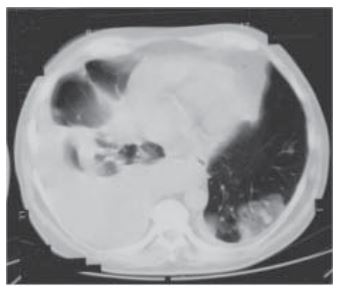

Los tumores cardíacos primarios constituyen una entidad rara. Sólo el 10% a 25% de ellos son malignos y el angiosarcoma es el más frecuente. Ocasionan sintomatología cardíaca y sistémica variada, por sí mismos o por compromiso de otros órganos, lo que puede simular otras patologías y derivar en un retraso del diagnóstico de certeza. Se describen dos casos de angiosarcoma cardíaco con presentaciones atípicas, por lo que inicialmente no se consideró esta patología como un diagnóstico probable. Se requiere un alto grado de sospecha clínica, junto con métodos por imágenes de alta resolución como la resonancia magnética, para la aproximación diagnóstica correcta y el tratamiento adecuado.